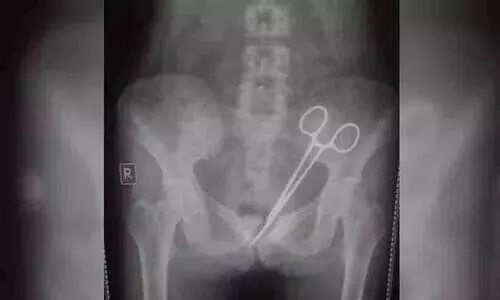

ഗ്യാങ്ടോക്: 12 വർഷം മുമ്പ് നടന്ന ശസ്ത്രക്രിയക്കിടെ ഡോക്ടർമാർ യുവതിയുടെ വയറ്റിൽ വെച്ച് മറന്ന കത്രിക കണ്ടെത്തി. കടുത്ത...